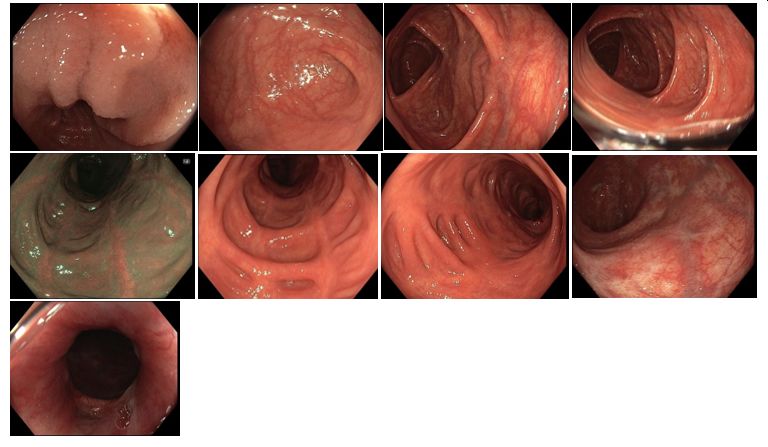

Koloskopie 2013/7: Endoskopický obraz těžké, segmentální pankolitidy. Plazivé ulcerace rekta, sigmoidea a descendens. Drobné afty c. transversum a céka. Normální nález v terminálním ileu

Koloskopie 2014: Endoskopický obraz mírné segmentální pankolitidy (aftózní léze, nálety fibrinu, reziduální drobné ulcerace po původně serpiginózních vředech). Nápadné pozánětlivé změny (jizvy, polypy), retrakce zejména v levém tračníku. Normální terminální ileum